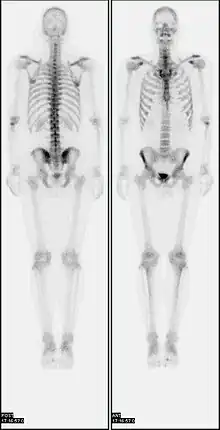

Scintigraphie osseuse

La scintigraphie osseuse est un examen de médecine nucléaire consistant à injecter à un patient un produit radioactif qui va se fixer sur le squelette. Cet examen permet d’obtenir des images qui sont le reflet du métabolisme osseux. Il est indiqué dans de nombreuses pathologies osseuses, notamment en cancérologie pour la recherche de métastases osseuses ou en rhumatologie[1].

La scintigraphie osseuse est pratiquée dans un service de médecine nucléaire. Une injection de biphosphonates marqués au technétium 99m est réalisée, le plus souvent au pli du coude. Ce produit radiopharmaceutique va se fixer dans le squelette, absorbé dans les cristaux d’hydroxyapatite de l’os minéral[3]. La fixation sera plus importante dans les zones dans lesquelles il existe une augmentation du remodelage osseux, en réponse à une agression tumorale ou traumatique. L’acquisition des images se fait au moyen d’une gamma-caméra pouvant être couplée à un scanner, permettant d’obtenir des images anatomiques en plus des images métaboliques de la scintigraphie.

Selon l’indication, des images précoces peuvent être réalisées dans les minutes suivant l’injection afin de rechercher une inflammation dans la zone douloureuse. Dans tous les cas, des images tardives sont réalisées deux à trois heures après l’injection[4], permettant de repérer les zones avec un hypermétabolisme osseux (ou hyperactivité ostéoblastique) dans lesquelles le produit injecté s’est accumulé.